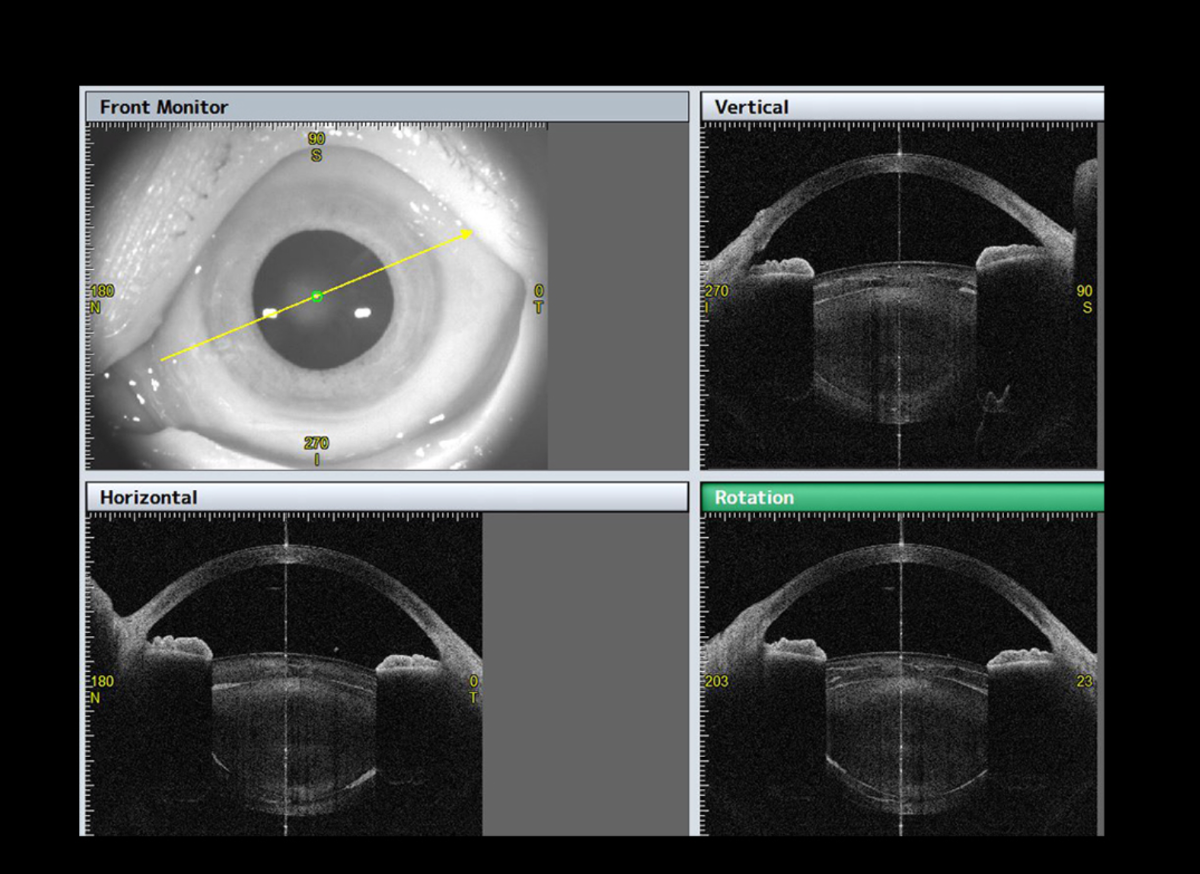

Pre- and Post-OP ICL function

Cataract

Our special Pre-op Cataract application guides you towards a very good preparation for your cataract surgery. The IOL screening prepares all essential and necessary data for your ideal IOL choice.

The unique Lens Analysis application provides you with all relevant lens parameters, including front and back radial curvature and the lens tilt and decentration. With this tool a precise prediction of your surgery result is guaranteed.

The Post-op application clearly visualises and documents the quality of your cataract surgery with all needed information for your ideal check-up.